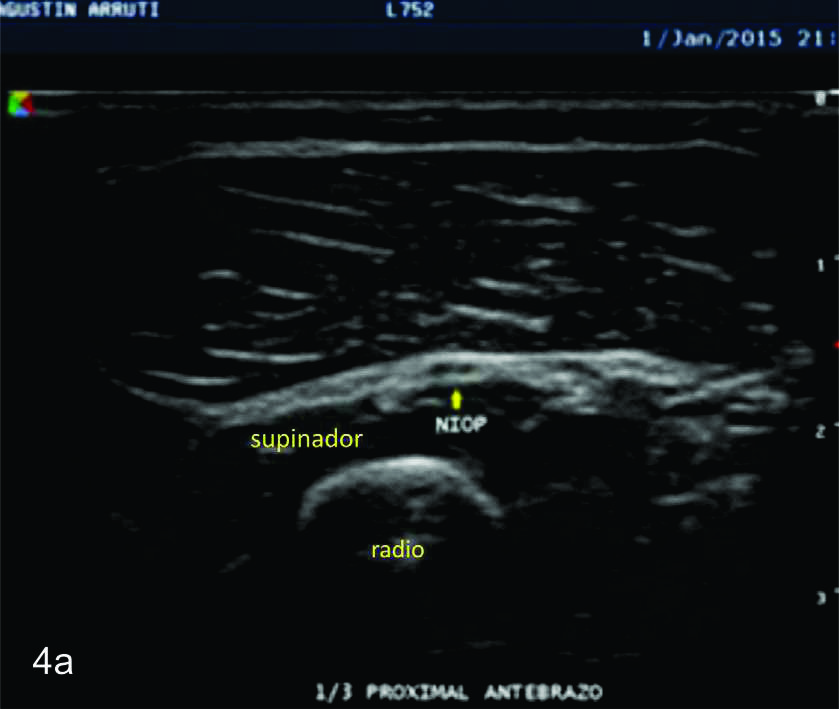

Figura 4

Nervio interóseo posterior

Serie de cortes axiales del nervio interóseo posterior, desde su origen a nivel del codo como rama terminal del nervio cubital hasta su terminación en la cara posterior del antebrazo. Se identifica el mismo señalado por flechas amarillas, supinador- Músculo supinador, flechas azules- ambas cabezas del supinador, flechas rojas- membrana interósea. A- tercio proximal antebrazo previo al ingreso al canal supinador, B- tercio proximal del antebrazo en el canal supinador entre los dos haces del supinador, C- tercio medio del antebrazo, localizado entre el plano muscular